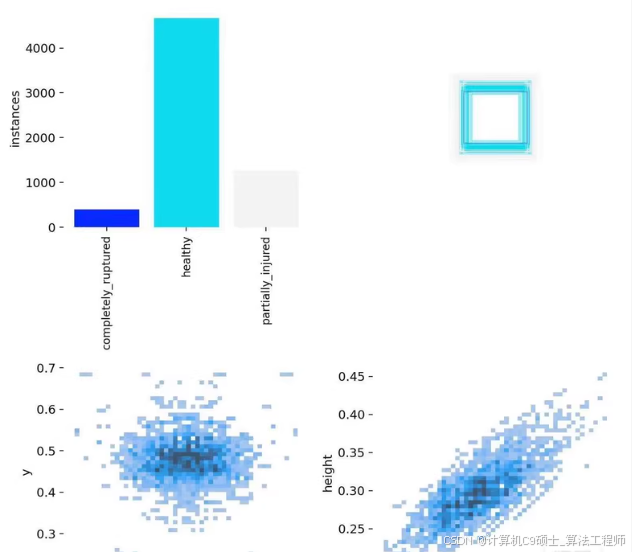

膝关节损伤程度目标检测数据集

-数据量: 7k张高质量图像

-目标类别(nc=3):

completely_ruptured’:完全断裂

‘healthy’:健康的

‘partially_injured’:部分受伤的

-格式(可选):YOLO格式(.txt)、VOC格式(.xml)